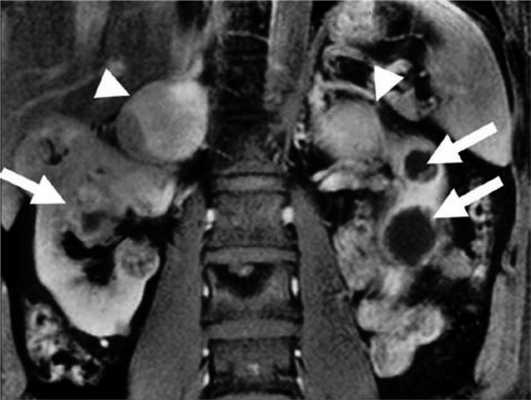

Феохромоцитома выявляется примерно у 26% пациентов с синдромом VHL [37]. У пациентов с очевидно спорадической феохромоцитомой в 3—11% случаев впоследствии выявляют мутацию VHL [10, 12, 13]. Феохромоцитома может быть первым проявлением синдрома [30, 72]. В большинстве случаев надпочечниковые феохромоцитомы при VHL-синдроме двусторонние (синхронные или метахронные) [37, 73]. Вненадпочечниковые феохромоцитомы встречаются примерно в 30% случаев [37, 74—76]. Феохромоцитомы как часть синдрома VHL имеют исключительно норадреналиновый фенотип. Биохимические маркеры опухоли могут помочь отличить VHL-ассоциированные феохромоцитомы от феохромоцитом при синдроме МЭН 2-го типа [75]. Различия в биохимическом фенотипе при VHL-синдроме и МЭН 2-го типа связаны с различной экспрессией тирозингидроксилазы (TH) — лимитирующего фермента синтеза катехоламинов, и фенилэтаноламин-N-метилтрансферазы (PNMT). У пациентов с синдромом VHL отмечена низкая экспрессия PNMT, преобразующей норадреналин в адреналин. Различия биохимического фенотипа также связаны с различиями хранения, транспорта и секреции катехоламинов [77]. МЭН 2-ассоциированные феохромоцитомы содержат более высокие концентрации катехоламинов из-за более выраженной экспрессии TH. VHL-ассоциированные феохромоцитомы, секретируют катехоламины непрерывно, тогда как при синдроме МЭН 2 отмечен эпизодический характер секреции. Это определяет и различия клинических проявлений двух синдромов. Например, пациенты с МЭН 2 чаще жалуются на кризовые подъемы АД [78]. Помимо генетических различий [26], регистрируется разная экспрессия эритропоэтина и его рецептора [79]. Кроме того, около 80% феохромоцитом бессимптомны и выявляются случайно при визуализирующих исследованиях. Низкая чувствительность некоторых радионуклидных методов визуализации может объясняться относительной нехваткой гранул хранения или уменьшенной экспрессией мембранного норадреналина или везикулярных моноаминных транспортеров [80]. Поэтому сцинтиграфия с 123 I-MIBG (метайодбензилгуанидином) часто не обнаруживает VHL-связанные надпочечниковые феохромоцитомы [81, 82]. ПЭТ с 6-18F-фтордопамином более чувствительный метод [36, 83]. Злокачественные феохромоцитомы с метастазами в легких, печени, костях, лимфоузлах редко встречаются при синдроме VHL [37, 74, 84—87]. Метастазы выявляются менее чем в 7% случаев [37]. К сожалению, в настоящее время нет четких признаков, позволяющих надежно отличить доброкачественную от злокачественной феохромоцитомы, хотя уже известно, что герминальная мутация гена SDHB, является в этом отношении точным маркером [86—88]. Выявление феохромоцитомы у пациентов с синдромом VHL особенно важно, учитывая высокую вероятность хирургических вмешательств по поводу других опухолей (гемангиобластом ЦНС и др.). Невыявленная феохромоцитома при других вмешательствах может привести к опасным для жизни гипертоническим кризам. Более 70% феохромоцитом у детей являются VHL-ассоциированными. Каждому пациенту с VHL-синдромом и подтвержденной феохромоцитомой до оперативного лечения необходимо проводить ПЭТ с 6-18F-фтордопамином или сцинтиграфию с 123 I-MIBG для выявления вненадпочечниковой феохромоцитомы или метастазов [89]. Лечение феохромоцитомы оперативное. В то же время 6-месячная терапия ингибиторами тирозинкиназы приводит к уменьшению опухоли на 21% и сокращению уровня норметанефринов и хромогранина А в плазме [90] (рис. 4). Рисунок 4. Двусторонняя феохромоцитома и поликистоз почек.

ФХЦ при болезни VHL чаще надпочечниковой локализации имеет исключительно норметанефриновый фенотип. Вненадпочечниковая ФХЦ встречается в 30% случаев. Приблизительно в 50% случаев опухоли являются двусторонними. Злокачественные ФХЦ встречаются редко [13].